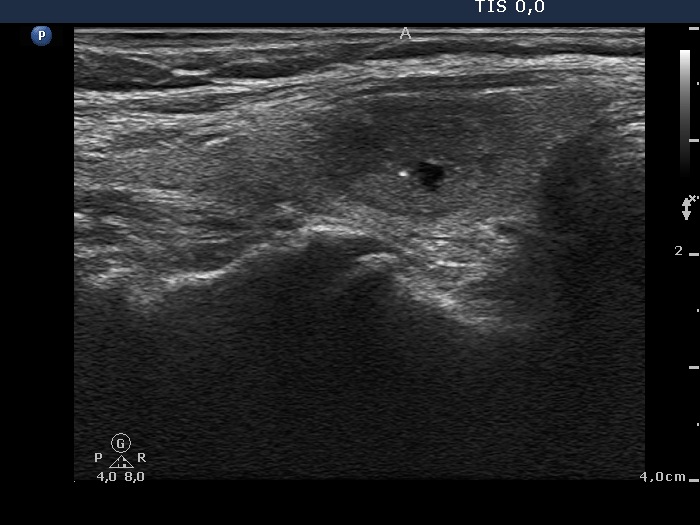

|

Papillary carcinoma (histological diagnosis) - case conp 035 |

The thyroid presented in the left images is composed of moderately hypoechogenic and hypoechogenic nodules, while the lobe in the malignant case is diffusely hypoechogenic and has a less hypoechogenic but more inhomogeneous lesion in its dorsal part. Both the left thyroid and the malignant nodule in the right images have hyperechogenic granules and lines which correspond to a connective tissue.